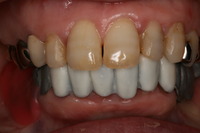

リーゲルレバーを閉じたところです。

お口にしっかりと固定され、びくともせずにしっかりと咬むことが出来ます。